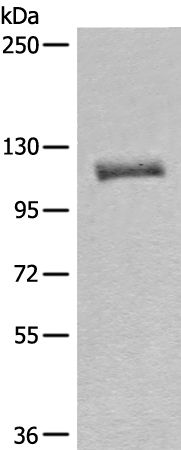

分类: 科研抗体货号: P07767别名: ACATE2; CGI-16; MTACT48; MT-ACT48应用: WB反应种属: Human, Mouse